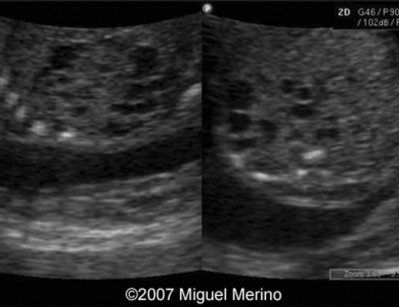

Ultrasonografías Varias

Envíado por Dr. Miguel Ángel Merino Araujo